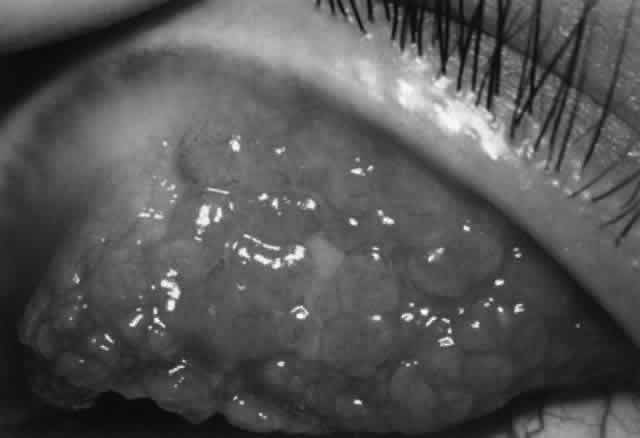

To provide a more standardized approach, the Collaborative Corneal Transplant Studies (CCTS) were undertaken.168 This multicenter effort showed no significant benefit of HLA-A, -B, and/or -DR donor-recipient matching on the rate of graft failure, on the rate of graft rejection, or on the rate of failure due to rejection in high-risk corneas. Also surprising was the finding that ABO matching resulted in a beneficial effect. The reasons for these unexpected findings are unclear and indicate our lack of understanding in this area. The CCTS suggest that HLA-DQ antigens may be important but have not been studied. Also, minor histocompatibility systems probably play a more significant role than previously thought. Furthermore, differences at the molecular level that cannot be detected by current serologic methods may be responsible. Another consideration is that the close follow-up and more intensive use of postoperative topical corticosteroids in this study may have played a role in the results.168 Thus, it is obvious that further research is needed.

Corneal Graft Rejection: Treatment

Corticosteroids are the mainstay of therapy of corneal graft rejection and fortunately are usually very effective. About 50% to 70% of rejection episodes can be reversed with topical corticosteroids.